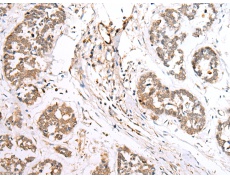

IHC positive control: |

Human tonsil and human esophagus cancer |

IHC Recommend dilution: |

30-150 |